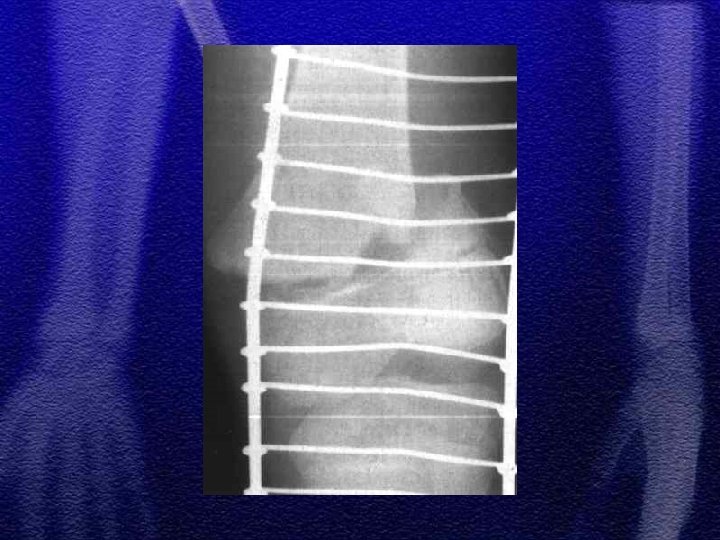

§ W obrębie powłok - zadrapania, wylewy krwawe, obrzęki w różnych stadiach gojenia, oparzenia, ubytki kępek włosów, naderwane uszy § złamania kości czaszki, żeber, kości długich w okolicach nasad i przynasad, związane z pociąganiem i skręcaniem kończyn - nawarstwienia okostnowe § złamania kompresyjne kręgosłupa mogą być wynikiem powtarzanego potrząsania dzieckiem